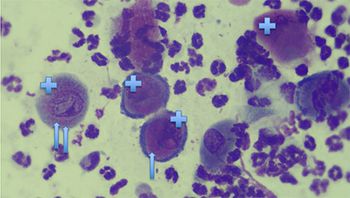

This skin impression cytology sample is from a 5-year-old, mixed-breed, spayed female dog.